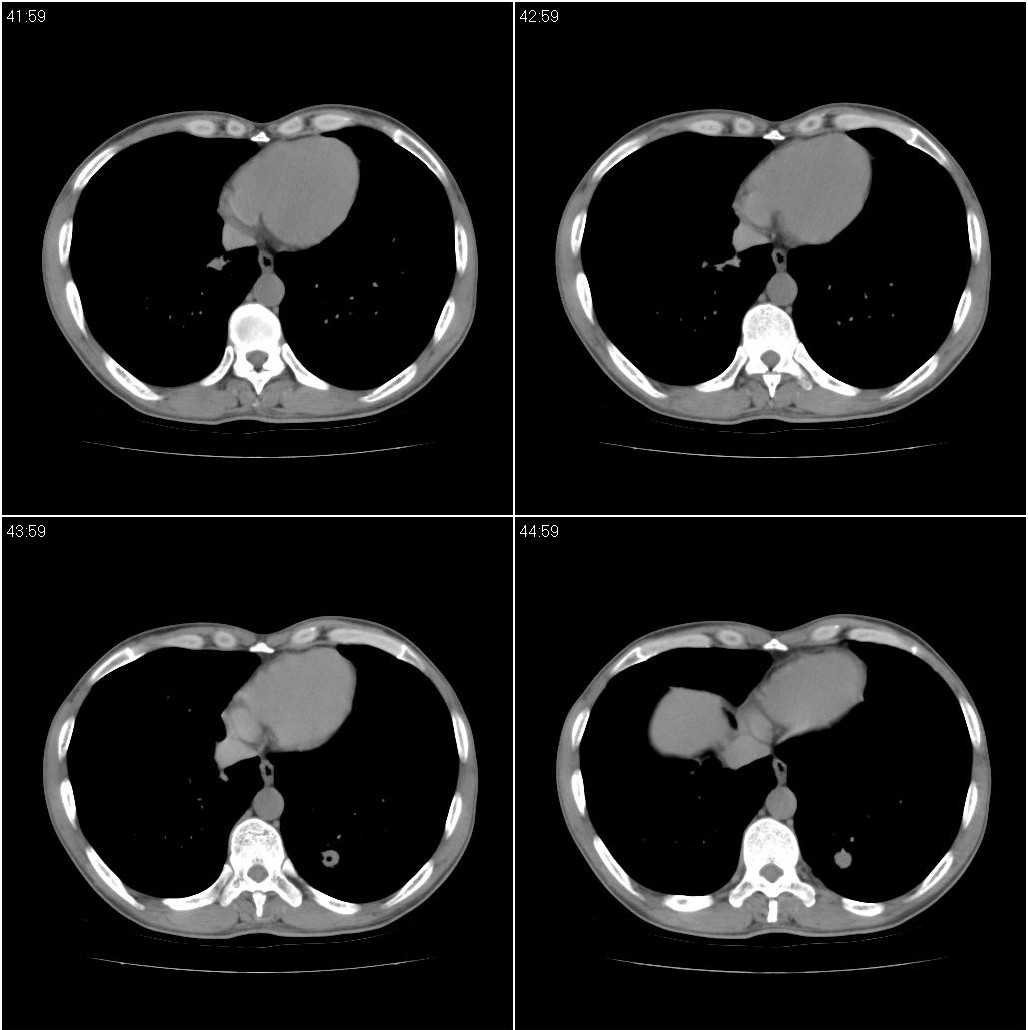

标题: CT23980:男性,47岁。近来咳痰、咳血,血沉增快(40左右),

男性,47岁。近来咳痰、咳血,血沉增快(40左右),痰中未检出结核杆菌。

两肺继发性肺结核并多发性结核球形成,部分病灶内空洞形成。